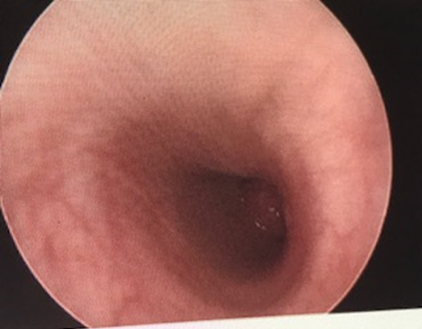

Flexible bronchoscopy and rigid bronchoscopy findings showed a polypoid, tan-colored mass in the distal left mainstem bronchus, with almost complete occlusion of the bronchus (Figure 3).

Figure 3. An obstructive endobronchial lesion at the distal entry of the left mainstem bronchus.